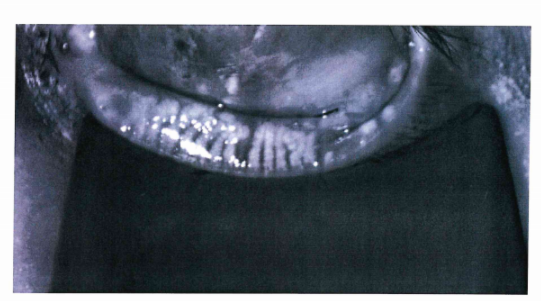

Above you can see the glands disappearing on the right side of the lower lid in this 11 year old boy who spends 3 hrs a day on an electronic device.